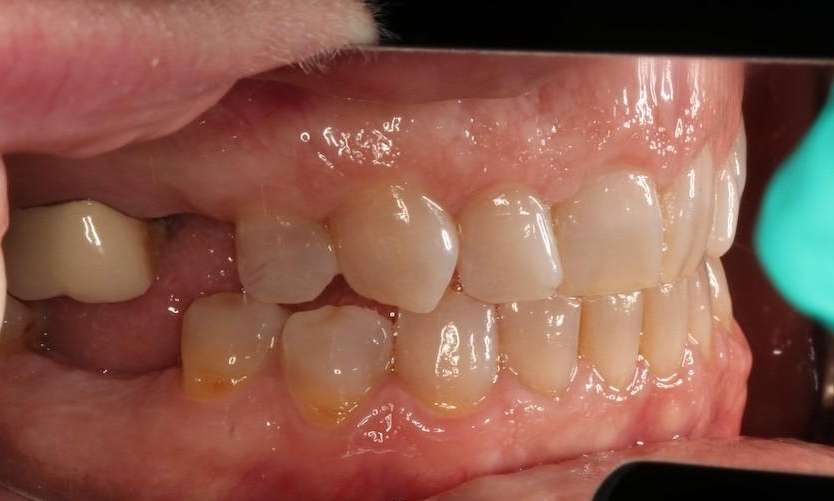

This patient was missing a molar and pre-molar, the workhorses for comfortable chewing. Without these stronger teeth at the back of your mouth, it becomes difficult to properly chew and eat your food.

Two dental implants saved the day by replacing both their root and tooth so this patient can comfortably chew their food again.

Close up of mouth before dental implants, nashville tn Close up of mouth after dental implants, nashville tn